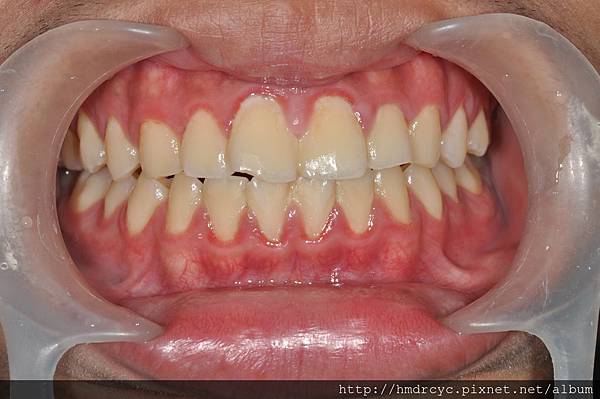

高雄的T先生有相同問題

單純牙肉發炎沒有骨頭吸收

洗牙治療兩天後 牙肉消腫回到原本位置